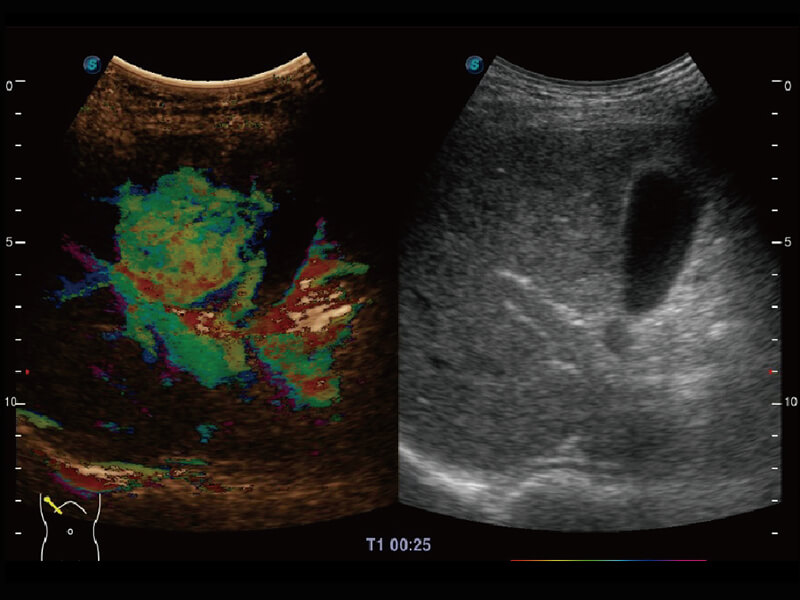

性能优异的硬件架构,极大提升超声系统的运行效率和数据处理能力。相比以往超声成像系统,Wis+平台为您带来极快的响应速度和成像帧频,提升检查流畅度。

S60探头工艺,从前端信号处理每一个环节采集无损声学数据,真实还原组织原貌,再现解剖细节。

超宽频带技术,为容积成像带来优质的二维图像基础,为您呈现丰富的结构细节,栩栩如生地展示宝宝的宫内形态以及各种组织的立体结构。